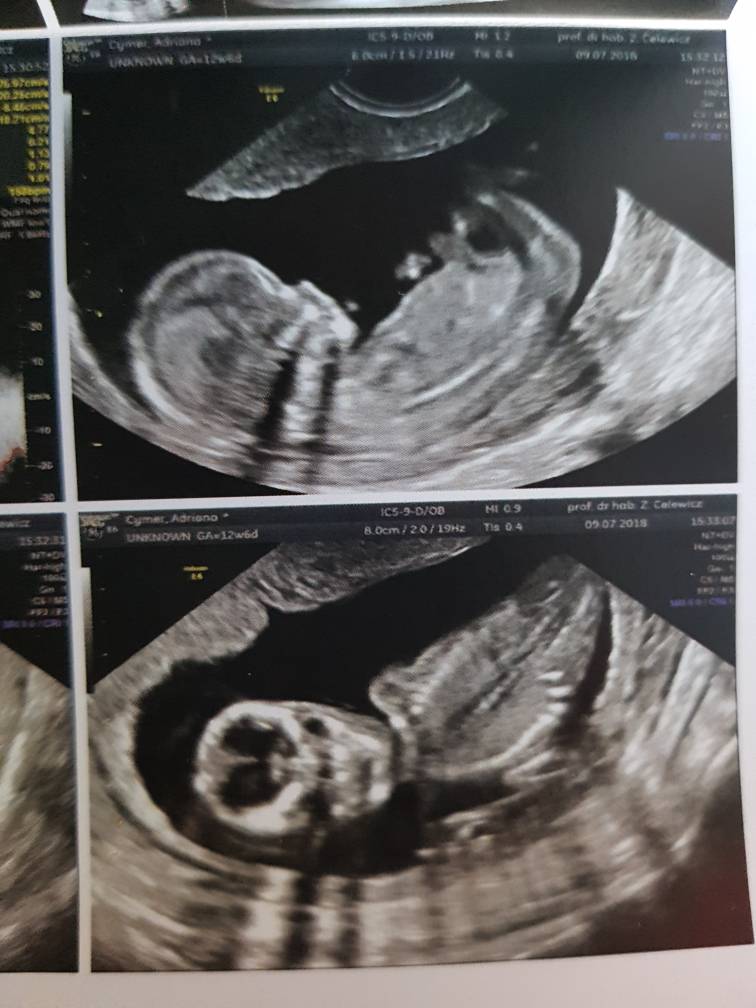

Mam 6.51cm taki już duży jestem :-)

Pięknie machałem do mamy i taty i ładnie współpracowałem z Panią doktor :-)

Pani doktor powiedziała, że wyglądam jej na chłopca i by się bardzo zdziwiła jeśli okazałoby się, że jestem dziewczynką ;) także jak na razie zostaję Mateuszkiem[emoji170] [emoji7] Co mamie się zgadza bo tak czuje[emoji12]

na USG wszystko w porządku, jeszcze tylko trzeba poczekać na wyniki z krwi ale mama jest dobrej myśli :)